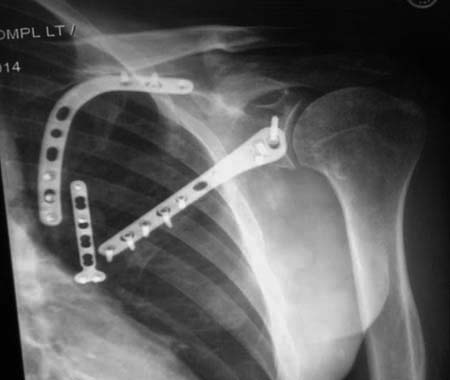

Здесь пример, стандартные снимки: плечо и лопатка прямой снимок,

аксиллярный и косой снимки (Y-view) и фиксация пластинами по краям, где

имеется более твердая кость. Специальные пластины, хотя любая 2.7 или

3.5 мм тубулярная пластина подойдут для фиксации перелома. Риск операции

- это повреждение нерва во время доступа и ре-фиксация ротаторной

манжетки если потребуется широкий доступ!